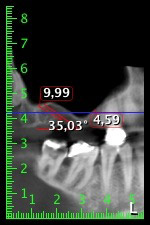

La paziente, 59 anni, presenta un caso di parodontite avanzata e descrive una sensazione di fastidio e scarsa sensibilità gustativa dal primo quadrante in direzione distale. L'esame clinico rivela tasche parodontali generalmente diffuse e un'atrofia ossea molto avanzata nelle regioni 16 e 14. L'esito è confermato dalla radiologia (fig. 1). Non è possibile salvare i denti 16 e 14.

Immagine 1: ortopantomografia con artrofia ossea nella regione 16–14. *